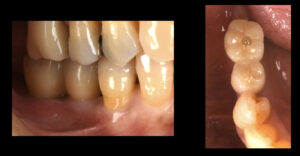

2023.05.12 奥歯複数歯 奥歯にインプラントを入れてしっかり噛めるようになった症例

- Before

- After

| 処置内容・方法 | 欠損部位にインプラントを2本入れた。 |

| 埋入箇所 | 下顎臼歯部 |

型取りから約2週、オペからは10週でセラミックの歯が入りました。なんでもしっかり噛めるようになり、大変喜んでいただけました。